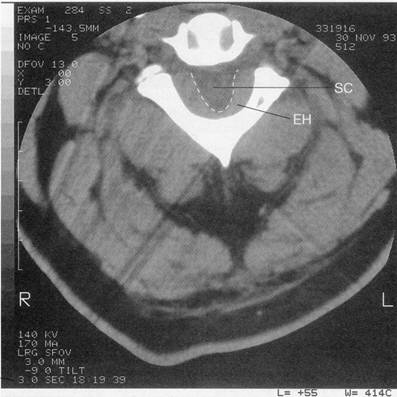

Evolução: A Sra. N. B. foi submetida à cirurgia no dia seguinte. O disco intervertebral foi removido entre as vértebras L5 e S1, sem incidentes. Foi-lhe prescrito um programa su-pervisionado de fisioterapia. Seis meses após a cirurgia, a paciente estava livre da dor e tinha retomado sua vida normal. Caso 9 A Sra. A. R. é uma mulher de 64 anos de idade que queixa-se de que o lado esquerdo do corpo está fraco e esquisito. Tem tremor há vários anos, e recentemente piorou tanto que ela foi ao médico da família. Este pediu uma consulta neurológica, porque pensou que ela havia tido um derrame. A paciente diz que se sente toda dura e que tem dificuldade para iniciar a marcha. Pisca raramente, e sua neta a chamava, brincando, de grande cara de pedra. Há quatro anos, a Sra. A. R. desenvolveu um tremor na mão esquerda. Ao longo de alguns meses, o tremor se espalhou para a perna esquerda. Diz que não teve a gripe espanhola, durante a grande epidemia da década de 1920. Não teve qualquer exposição, ocupacional ou social, a níveis tóxicos de monóxido de carbono, manganês, dissulfito de carbono, ou MPTP. Nunca foi tratada com fenotiazinas, reserpina, haloperidol, ou substâncias semelhantes. Não há histó-ria de doença neurológica na sua familia. O exame neurológico revelou que a paciente está alerta, espirituosa e conversa muito bem. Orienta-se quanto ao tempo e ao espaço. Pode fazer subtrações seriadas de sete e sabe os nomes de alguns presidentes do Brasil. Não há déficits de memória. Todas as funções dos nervos cranianos estão dentro dos limites normais. Apesar de sua voz ser muito suave, não há indicação de rouquidão. Os movimentos extra-oculares são plenos, simétricos e bem coordenados. A fisionomia de A. R. é sem expressão, mesmo quando envolvida em conversação animada ou contando uma anedota. Não ajusta sua postura, nem faz muitos movimentos subconscientes, quando sentada na cadeira. Quando de pé, sua postura é curvada, mantendo os braços ligeiramente aduzidos e fletidos. Tem marcha arrastada e não balança os braços enquanto anda. Quando se vira, fica no lugar e arrasta os pés, girando em torno de um ponto único, como se estivesse sobre um pedestal. Todos os seus movimentos são lentos e deliberados. A avaliação da motricidade mostra que a força é +5 em toda parte. Há rigidez em roda dentada bem desenvolvida nos braços e nas pernas. Está um pouco mais rígida do lado esquerdo do que do direito; não há sinais de espasticidade ou clônus. Não há atrofias musculares. Há tremor óbvio de repouso de 3 a 5 Hz em todas as extremidades. O lado esquerdo está pior que o direito. Durante os movimentos voluntários, o tremor diminui ou mesmo desaparece. Não há fasciculações. Sua percepção da picada do alfinete e do toque com algodão e simétrica e dentro dos limites normais. Os reflexos de estiramento muscular estão todos dentro dos limites normais e são simétricos. Os sinais plantares são em flexão. Não foram testados coordenação e equilíbrio. O reflexo optocinético está presente, tanto para a esquerda quanto para a direita. Não há afasia ou negligência. O diagnóstico clínico definiu-se como doença de Parkinson. Evolução: A Sra. A. R. está tomando um medicamento (Sinemet) que combina carbi-dopa e L-dopa, no mesmo comprimido. A carbidopa é um inibidor da descarboxilase, que não cruza a barreira hemato-encefálica. Impede a conversão da L-dopa em dopamina na circulação sistêmica, enquanto permite que a conversão ocorra na circulação cerebral. Essa combinação reduziu, de muito, os efeitos colaterais associados à L-dopa isolada. A Sra. A. R. está passando bem. Seu desempenho motor geral é mais lento que o normal, mas ela é capaz de caminhar sem ser assistida e de desempenhar todas as atividades da vida diária. Está morando sozinha e tem vida social ativa. Caso 10 O Sr. B. T., um homem com 52 anos de idade, foi levado ao hospital por sua família, depois de se tornar delirante e confuso durante o piquenique familiar em dezembro. Não obs-tante a temperatura estar nos 30ºC, o Sr. B. T. estava com frio e pediu um cobertor. Pensando que ele estava brincando, a família ignorou seu pedido. Mais tarde foi encontrado enrolado em um cobertor, tremendo e delirante. No departamento de emergência, o Sr. B. T. não estava mais delirante. Estava tremendo violentamente e enrolado nos três cobertores que tinha pedido às enfermeiras. O exame físico revelou pressão arterial de 132/82, 97 de pulso, e temperatura de 39,5ºC. Ele não estava transpirando. O exame do estado mental mostrou que o Sr. B. T. estava acordado, alerta, e orientado quanto à data, ao tempo e ao lugar. Disse que sua familia pensou que ele delirava, porque tinha pedido um cobertor. Afirmou que estava apenas com muito frio. Tinha consciência de que era um dia muito quente de dezembro. Disse que sabia por que estava com frio. Podia fazer subtrações seriadas de sete e lembrar os nomes de alguns presidentes do Brasil. Ao final do exame, foi capaz de lembrar dos três itens que lhe haviam pedido que memorizasse. A avaliação dos nervos cranianos revelou os seguintes achados: OLFAÇÃO: o paciente podia detectar e identificar corretamente silicato de metila por ambas as narinas; VISÃO: havia uma densa hemianopsia bitemporal ao exame de confrontação; MOTI-LIDADE OCULAR: ele podia seguir o dedo, em movimento, do examinador, em todas as dire-ções. Não havia nenhuma fraqueza óbvia de qualquer um dos músculos da motilidade ocular ou nistagmo. As respostas pupilares estavam presentes e consensuais a partir de ambos os olhos. Não havia ptose; TRIGÊMEO: as sensações do algodão e da picada do alfinete estavam presentes e simétricas em todas as divisões. O reflexo corneano estava presente. Os músculos masseteres eram iguais; FACIAL: a careta era simétrica e plena. Os olhos pareciam normalmente hidratados; AUDIÇÃO: aparentemente normal ao esfregar dos dedos; VAGO GLOSSOFARÍNGEO: a voz estava normal. Arcos faríngeos altos e simétricos. Úvula na linha média. Reflexo do vômito presente; ACESSÓRIO: os músculos esternocleidomastóideo e o trapézio pareciam ter força normal e eram simétricos; HIPOGLOSSO: a língua era protruída na linha média. Não havia fasciculações ou atrofia. A avaliação da postura e marcha mostrava ser marcha normal. Marcha emparelhada, o pular, o teste de Romberg, calcanhar-joelho e dedo-nariz, todos realizados sem dificuldade. O exame da motricidade revelou que a força era 5/5 em todas as extremidades e articulações. Não se observou desvio. Não havia espasticidade ou rigidez. O volume muscular era simétrico e apropriado. Não foram observados movimentos anormais. A percepção da picada do alfinete e do algodão estava presente e simétrica em todas as áreas. O teste de Romberg era normal. Todos os reflexos de estiramento muscular estavam dentro dos limites normais e eram simétricos. Sinais plantares em flexão. As provas dedo-nariz, calcanhar-joelho, movimentos alternantes rápidos das mãos e dos dedos, foram todas realizados sem difi-culdade. Ausência de afasia ou de sinais atavísticos. Comentário: Encontrar o Sr. B. T. tremendo e enrolado em três cobertores em um dia quente de dezembro poderia sugerir que ele estivesse delirante ou histérico. No entanto, uma doença psiquiátrica é menos provável, à luz da hemianopsia bitemporal revelada durante o exame neurológico e da ausência de sudorese, apesar de sua temperatura corporal elevada. A tomografia computadorizada do crânio revelou grande massa ao nível do quiasma óptico, con-firmando assim o diagnóstico de proceso expansivo compressivo da região paraselar. Evolução: Foi realizada uma craniotomia, e a massa foi removida com sucesso. O Sr. B. T. recuperou-se da cirurgia, sem complicações. O paciente mudou-se subseqüentemente da região em que morava e sua evolução não foi mais acompanhada. Caso 11 O Sr. G. P., um jardineiro com 36 anos de idade, foi visto no departamento de emer-gência, porque um grande galho de árvore caíra sobre sua cabeça, quando estava podando a árvore com uma motosserra. O galho empurrou seu peito sobre o cabo da serra, e a lâmina da serra se enterrou-se no chão. Ele queixou-se de dores no peito e nas costas, e de cefaléia. A laceração de 8 cm no couro cabeludo occipital foi reparada. A radiografia da espinha cervical e o exame neurológico produziram achados normais. Ele recebeu alta. Então, 48 horas mais tarde, o Sr. G. P. tomou aproximadamente 12 comprimidos de 200 mg de Ibuprofeno, em bre-ve período de tempo, por causa da dor inter-escapular que piorava. Cerca de quatro horas mais tarde, 52 horas depois da lesão inicial, queixou-se de piora súbita da dor nas costas, que se irradiava para o peito e os ombros. Caiu ao chão, incapaz de mover as pernas, queixando-se de dormência nas mesmas. Era capaz de mover os braços e os dedos do pé esquerdo. Quando foi trazido ao departamento de emergência, por ambulância, ele tinha perdido toda a atividade motora das extremidades inferiores e observou formigamento nos braços. Ao longo das duas horas em que esteve no departamento de emergência e no serviço de radiologia, desenvolveu fraqueza da preensão manual. O exame físico mostrou pressão arterial de 160/95 e 12 respira-ções laboriosas por minuto. O exame neurológico revelou que o Sr. G. P. está desperto, alerta e orientado quanto à pessoa, tempo e lugar. Não foram observadas anormalidades na função dos nervos cranianos. Não foram testadas postura e marcha. O exame da motricidade revelou que a força era 0/5 em todos os grupos musculares de ambas as extremidades inferiores; a força da preensão manual e da flexão do punho era 4/5. O tônus muscular era flácido em ambos os membros inferiores. O tônus dos membros superiores era normal. Volume muscular normal para um homem trabalhador de sua idade. Não havia atrofias. Não foram observados movimentos anormais. Há perda sensorial completa à picada do alfinete e ao toque leve do algodão, do nível de C7-T1 para baixo. Os reflexos de estiramento muscular do bráquio-radial, bíceps e tríceps são normais bilateralmente. Os reflexos do gastrocnêmio e do quadríceps estão ausentes bilateralmente. Não há resposta à estimulação plantar. Os reflexos cremastérico e abdominais estão ausentes bilateralmente. Há movimento abdominal paradoxal à respiração. Não há tônus retal, e o reflexo anal está ausente. Não foram testados coordenação e equilíbrio, assim como funções parietais. A radiografia e a tomografia computadorizada da coluna torácica produziram achados normais. A TC da coluna cervical sugeria hematoma epidural de C6 a C7. A mielografia revelou um longo hematoma epidural circunferencial, estendendo-se de C2 a T3, com bloqueio quase completo de C6 a C7 (vide figura). Evolução: O paciente foi imediatamente levado à cirurgia, quando foi feita laminec-tomia de C3 a T3 para aliviar a pressão sobre a medula espinhal e evacuar o hematoma. Na sala de recuperação, o Sr. G. P. observou movimentos normais de seus braços e dedos. Durante as duas semanas subseqüentes, teve recuperação completa de suas funções motoras e sensoriais na ordem inversa da paralisia ascendente.